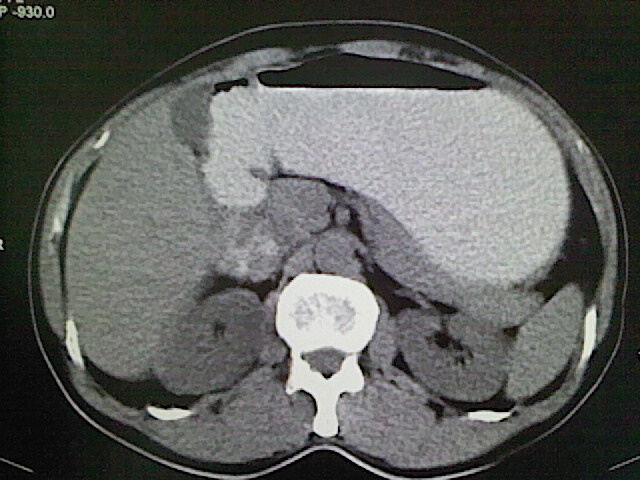

标题: CT18630:男,54岁,乙肝,大家看怎么样? [打印本页]

男,54岁,乙肝,大家看怎么样?

肝脏的要有增强敢说话

未见明确异常;建议必要时行ct增强扫描检查。